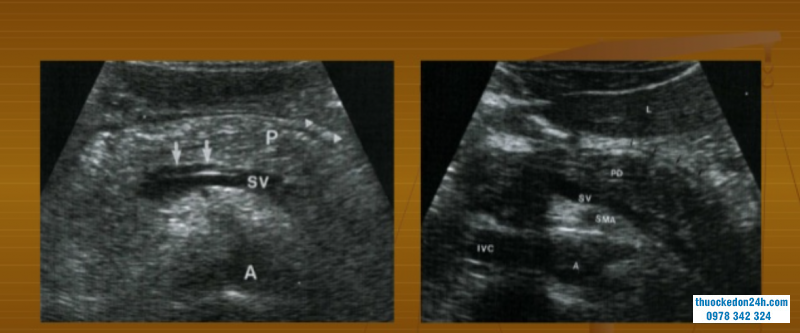

Hình ảnh viêm tụy cấp trên siêu âm bụng có thể đánh giá như sau:

Khi mắc phải chứng viêm tụy cấp, chủ mô tụy sẽ sưng phù nề khá to. Ống tụy chính(ống Wirsung) có thễ bị dãn. Hơn nữa các kiểm tra sẽ kết luận rằng lượng dịch ổ bụng khá ít. Đặc biệt là hình ảnh mỏng hơn so với gan. Khi mắc viêm tụy cấp có thể năng do sự bào mòn mạch máu, xuất huyết mô kẽ hay hoại tử ở chủ mô tụy.